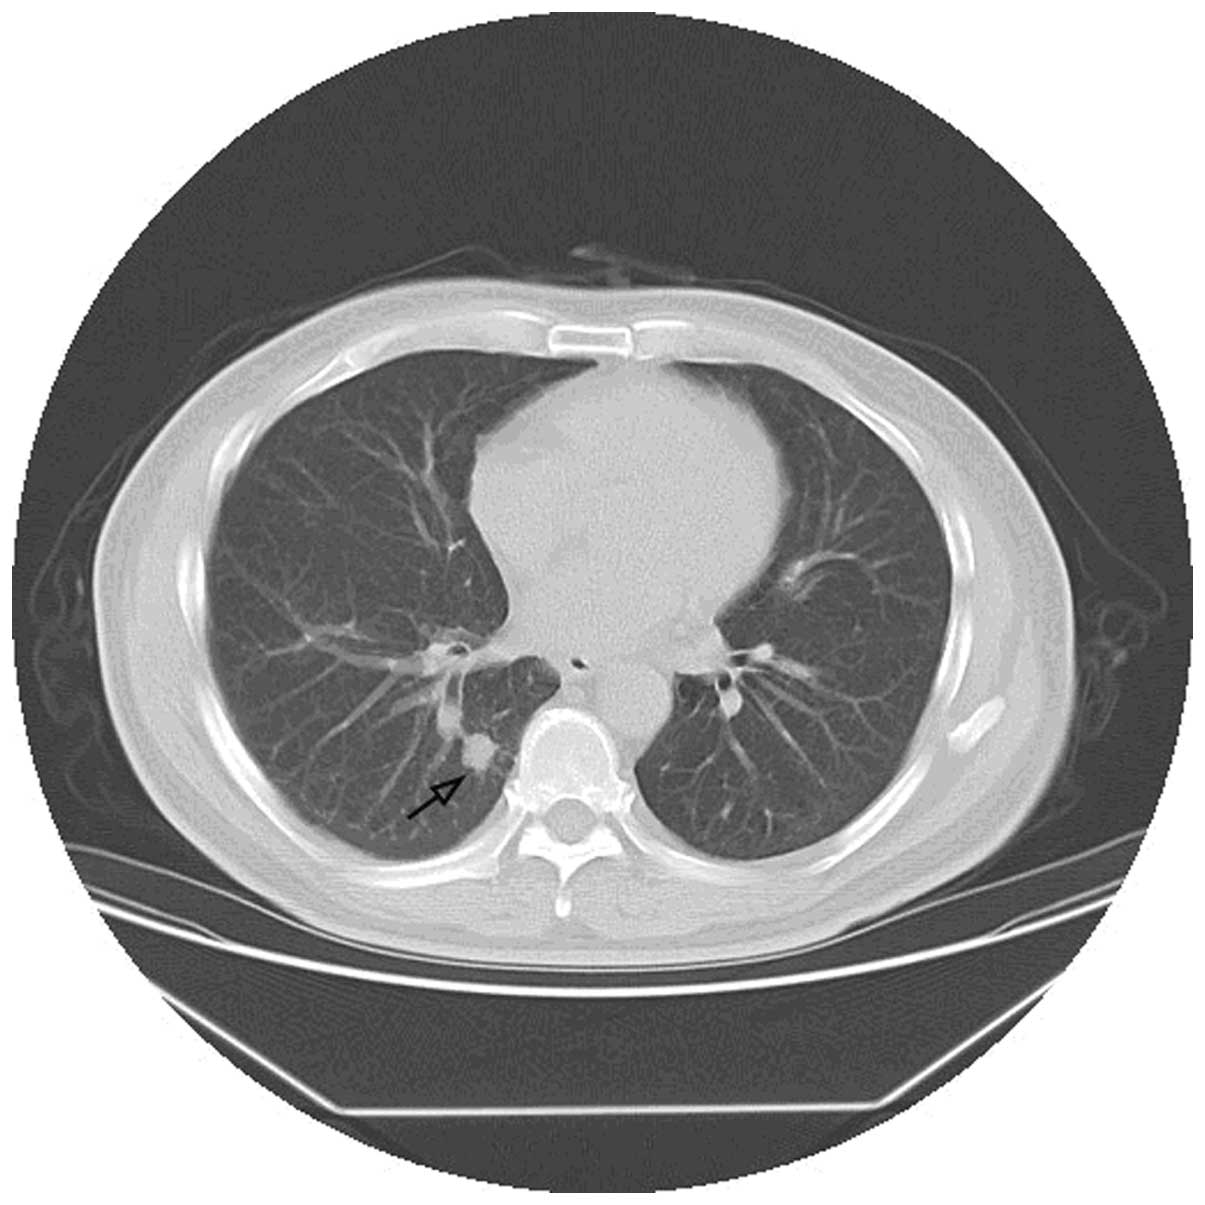

The current study reports the case of a 61‑year‑old man with diabetes who was suffering from generalized pain over the whole body and gradually progressive numbness. The patient was initially diagnosed with diabetic peripheral neuropathy and received treatment, however, the symptoms persisted. In October 2010, the patient was admitted to the Chinese People's Liberation Army Navy General Hospital (Beijing, China) for the treatment of diabetes, however, a full‑body sharp pain was also described, which was relieved upon massaging the area. Causes, other than diabetes, were investigated for these symptoms. Chest computed tomography and positron emission tomography‑computed tomography scans revealed a mass shadow in the right lower lobe of the lung, with multiple lymphatic metastases. Lung cancer was diagnosed with a tumor‑node‑metastasis stage of T1N3Mx. Following treatment of the cancer with chemotherapy and radiotherapy, the patient's symptoms were significantly improved. The present study reports a rare case of a paraneoplastic neurological syndrome (PNS) that presented as painful neuropathy resulting from lung cancer, which mimicked diabetic peripheral neuropathy.

Figure 1

Figure 2